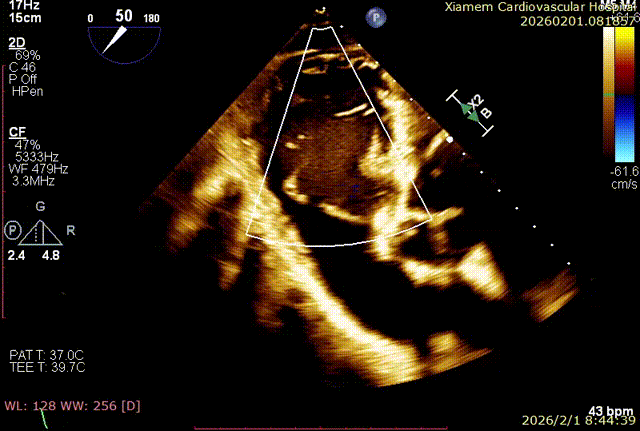

T-TEER 手术过程术前 TTE+TEE 评估:全心扩大,右房横径 8.3cm,左房横径 5.2cm;三尖瓣房性功能性反流,Type ⅢB 型(后叶为两瓣),反流程度 4+(Massive),缩流颈宽度 VC 为 14.5mm;TAPSE 为 1.3cm, LVEF(%)为 72%。

术前食道中段切面

食道胃底切面